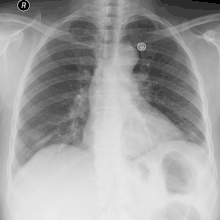

La radiographie thoracique de face et de profil est faite avant la ponction[14],[20]. Elle peut retrouver soit un épanchement pleural libre, soit un épanchement enkysté.